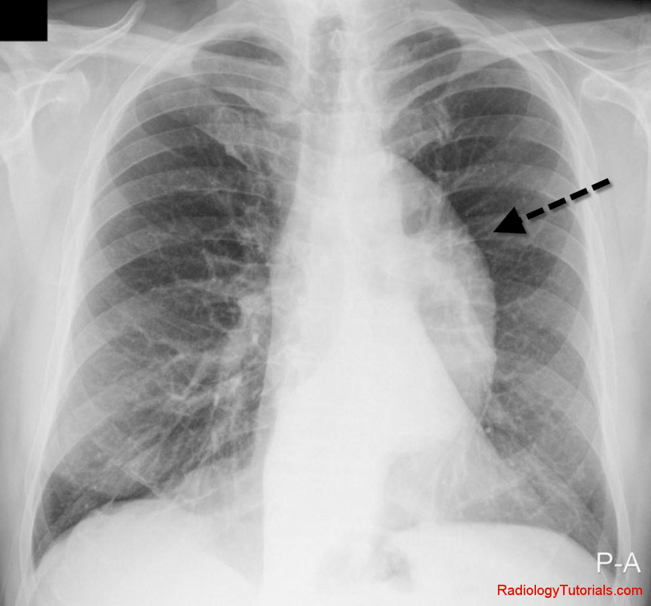

The Calcium Sign Is A Finding On A Chest X-ray That Suggests Aortic... | Download Scientific Diagram

aortic ray calcium sign chest dissection finding calcification suggests figure publication

calcium sign chest double pain thebluntdissection wikiradiography courtesy